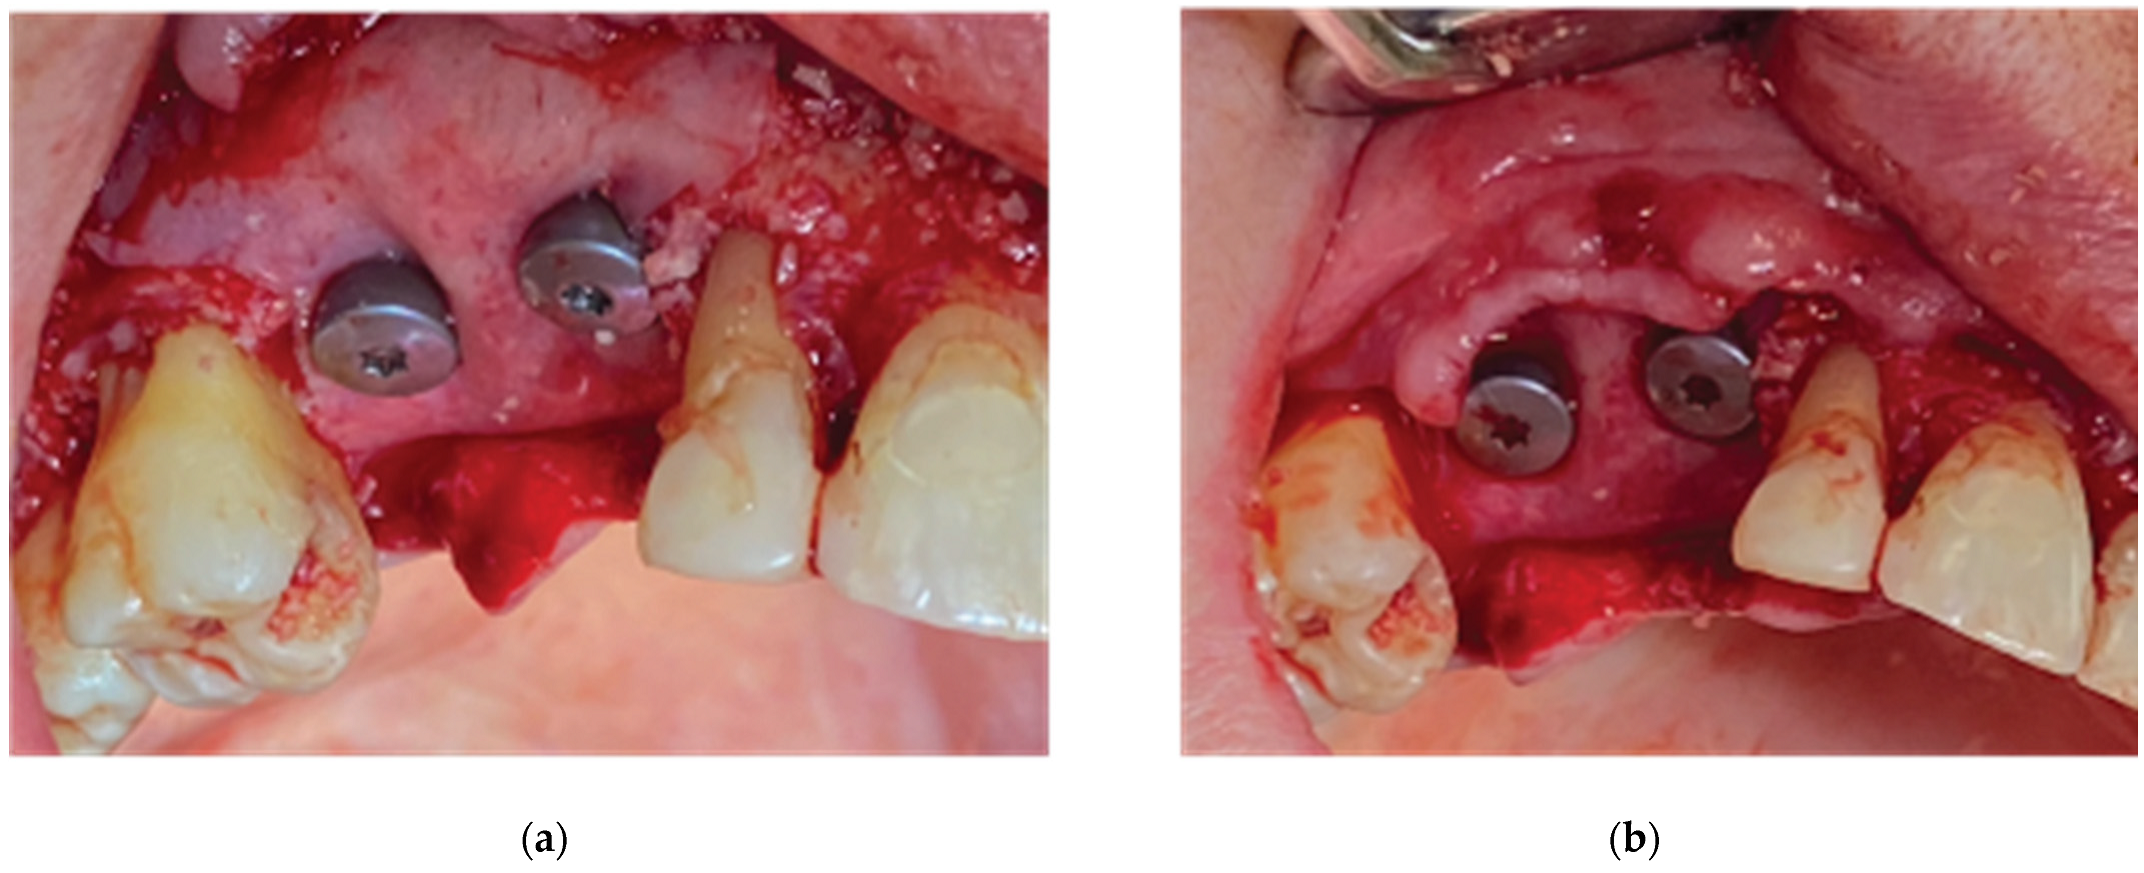

2.1. Case 1

2.2. Stage 1